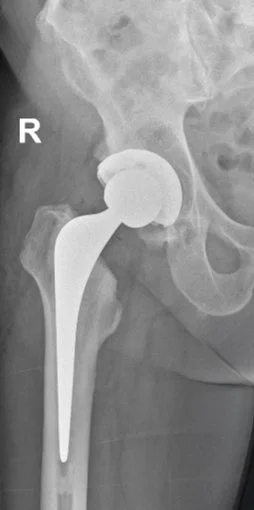

A total hip replacement (hip arthroplasty) involves removing the damaged ball (femoral head) and socket (acetabulum) of the hip joint and replacing them with smooth, artificial components made from metal, ceramic, or highly durable plastic.

The hip is a ballandsocket joint, designed to carry weight and move freely in multiple directions. When arthritis or injury destroys the cartilage lining, the joint becomes painful, stiff, and unstable. A replacement restores smooth movement, aligns the leg properly, and significantly relieves pain — dramatically improving mobility and daytoday quality of life.

• Artificial implants made of cobalt chromium and titanium alloys are positioned to recreate the joint surfaces and restore alignment and function.

• The femoral stem will be inserted into the femur (thigh bone), and the new acetabulum is placed into the pelvis. These can be either uncemented or cemented depending on your bone quality.

• The femur is fitted with an artificial stem, topped by a metal or ceramic ball, and the acetabulum is lined with a plastic, metal, or ceramic cup.

• Steps are taken to achieve correct leg length, mobility, and joint stability as this ensures stable function and longevity of the hip implant.